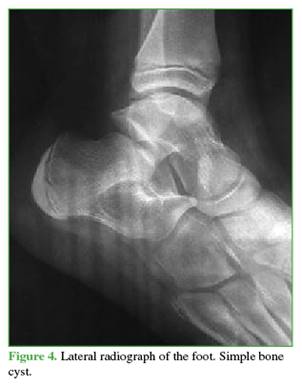

The differential diagnoses of a benign polylobulated calcaneal tumor included a simple bone cyst (Figure 4), an ABC (Figure 5), or an intraosseous lipoma (Figure 6).